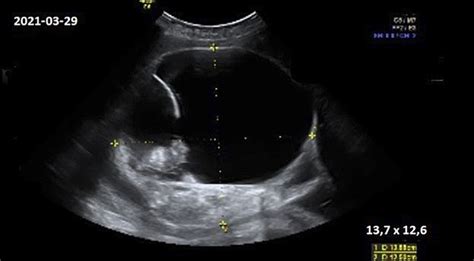

Tik ultragarsinis tyrimas gali nustatyti ir patvirtinti kūdikių skaičių gimdoje. Ultragarsas yra vienintelis patikimas būdas anksti nustatyti daugiavaisį nėštumą, dažniausiai jau nuo 8-os nėštumo savaitės. Pirmąjį ultragarsinį tyrimą rekomenduojama atlikti 11-14 nėštumo savaitę, kai vaisiaus ilgis (CRL) yra 45-84 mm. Atliekant šį tyrimą, patikslinama nėštumo trukmė, nustatoma, kiek yra vaisių, išmatuojamas jų dydis, ieškoma chromosomų anomalijų požymių ir didelių vaisiaus raidos ydų.

Nustačius dvynių tipą (identiški ar broliški), sudaromas tolesnis nėščiosios priežiūros ir ultragarsinių tyrimų planas. Jei dvyniai neidentiški, kiti ultragarsiniai tyrimai atliekami maždaug kas keturias savaites, jei nenustatomos komplikacijos. Jei laukiamasi identiškų dvynių, ypač tų, kurie dalijasi bendra placenta, tyrimai atliekami dažniau - kas dvi savaites, nuo 16-os nėštumo savaitės, siekiant laiku pastebėti galimas komplikacijas, tokias kaip dvynių transfuzijos sindromas. Jei ultragarsu nustatomos komplikacijos, moteris nukreipiama į perinatalinį centrą.